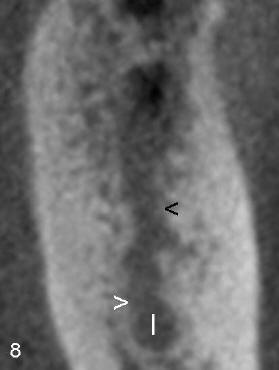

Cross sections through the furcae of #30 and 19 re-confirm that trabecular patterns are normal under the furca of #30 (< in Fig.7), whereas there is abnormal communication between PARL (above black < in Fig.8) and the inferior alveolar nerve (I).